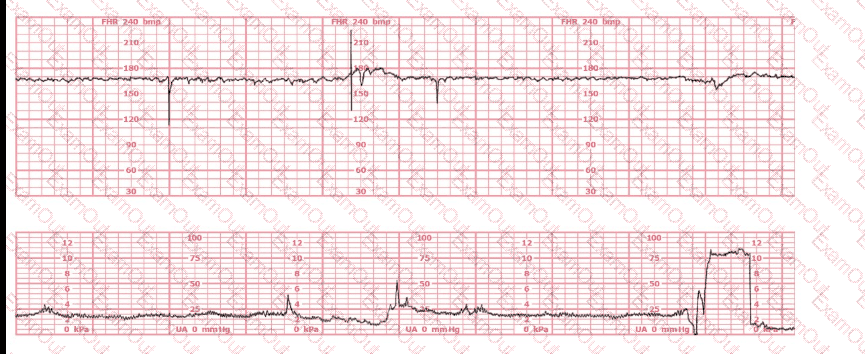

A woman at 39-weeks gestation is in early labor, 2–3 cm dilated, 85% effaced, and –2 station. Based on the fetal heart rate tracing shown, what is the most appropriate first intervention?

Based on the tracing shown, the first action should be to

palpate for contractions

The pattern on the fetal heart rate tracing shown is likely due to

fetal head compression

placental insufficiency

umbilical cord compression